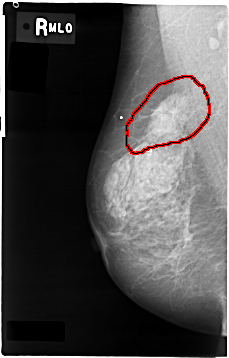

C_0004_1.RIGHT_MLO

FILE: C_0004_1.RIGHT_MLO.OVERLAY

TOTAL_ABNORMALITIES 1

ABNORMALITY 1

LESION_TYPE MASS SHAPE IRREGULAR MARGINS SPICULATED

ASSESSMENT 5

SUBTLETY 5

PATHOLOGY MALIGNANT

TOTAL_OUTLINES 1

BOUNDARY